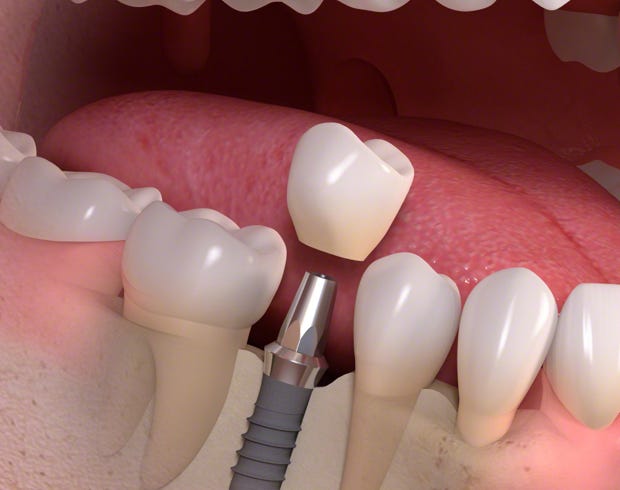

Wenn ein Zahn und seine Wurzel fehlen, ist die langfristige Lösung für eine natürliche Funktion ein Dentalimplantat mit dazu passender Krone.

Über Zahnimplantate

Ein Dentalimplantat ist ein kleiner, aber stabiler Pfosten aus biokompatiblen Metallen oder Keramiken. Es wird unter Lokalanästhesie anstelle der fehlenden Zahnwurzel in den Kieferknochen gesetzt und fungiert als Stütze für den Zahn.

Die Einheilphase dauert zwischen 6 und 12 Wochen, abhängig von der individuellen medizinischen Situation. Während dieses Zeitraums wird das Implantat sicher im Kieferknochen befestigt – ein als Osseointegration bezeichneter Prozess. Nach der Einheilung fungiert diese künstliche Wurzel als Basis für die Befestigung einzelner Kronen, mehrgliedriger Brücken oder einer Totalprothese.